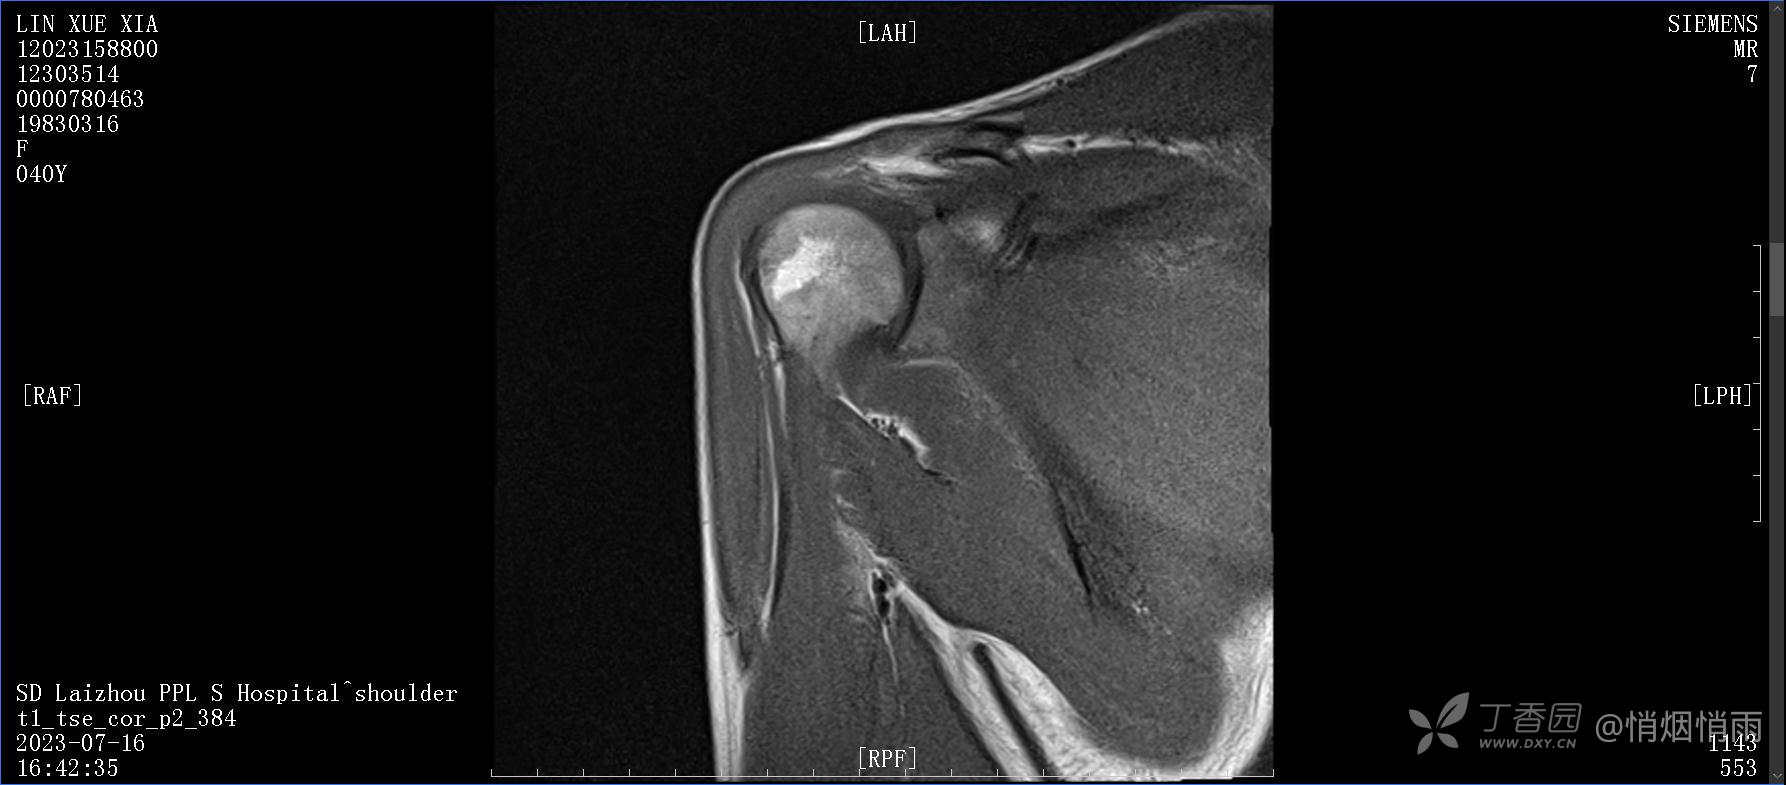

查体:右肩关节局部轻度肿胀,肩胛区压痛明显,痛处不固定,肩关节痛性活动受限,jobe test(+),lift -off test(+),中指、环指感觉较余指减退,余肢端感觉及血运情况可。

目前的诊断,暂时依据辅助检查诊为肩袖损伤,但是患者疼痛的性质和特点,却不是单纯的肩袖损伤所致。考虑过胸廓出口综合征,但是该疾病会出现肩胛区的疼痛吗?(由于考虑到费用的问题,没再进行下一步的检查)带状疱疹会有如此的症状吗?